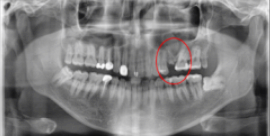

먼저 치아 엑스레이를 촬영하였고, 현재 치아의 상태에 대해 살펴보았습니다.

확인해 보니, 좌측 상단의 치아가 딱딱한 음식을 씹으며 치아가 떨어졌지만, 뿌리가 남아있는 상태로, 발치를 먼저 진행해야 하는 상황이었습니다.

임플란트 1차 치료 후

2021.07.23 / 2021.08.02 (1차,2차 후)

환자분은 상담 1주일 후 내원을 해주셨습니다. 발치와 함께 임플란트 1차 치료가 진행되었습니다.

임플란트 뿌리가 되어줄 '인공치근'을 심었습니다.(1차 치료) 그 후 일주일 뒤 보철과 인근치근을 연결해 주는 지대주를 식립하셨습니다. (2차 치료)